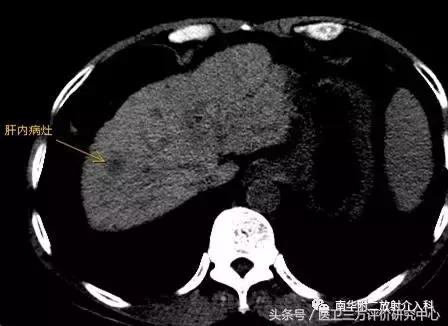

消融术前肝内病灶

患者曹某,男,63岁,有乙肝肝硬化,近3月来血AFP持续增高,我院CT及MRI增强扫描示肝SⅧ段占位,拟诊小肝癌,跟病人及家属商议后决定行微波消融治疗;遂于昨日下午在CT引导、局部+静脉联合麻醉下顺利完成了微波消融术治疗。手术时间约45分钟,术后患者未诉特殊不适,现恢复良好,已可下床自由行走。在此特别感谢麻醉科、消化内科及介入室老师的鼎力支持!